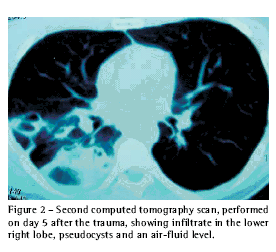

Five days after admission, the patient developed fever and purulent expectoration. A second CT scan of the chest revealed improvement of the pneumothorax, decreased condensation in the lower right lobe and pseudocysts with an air-fluid level in the same lobe (Figure 2). After blood, urine and sputum cultures had been collected, a course of antibiotics (amoxicillin + clavulanic acid and ciprofloxacin) was started. In the sputum culture, growth of b-hemolytic Streptococcus was observed. On day 15 after admission, the patient presented clinical improvement and normal laboratory exams and was discharged. The CT scan performed on the day of discharge revealed significant clinical improvement in relation to the preceding exam (Figure 3).